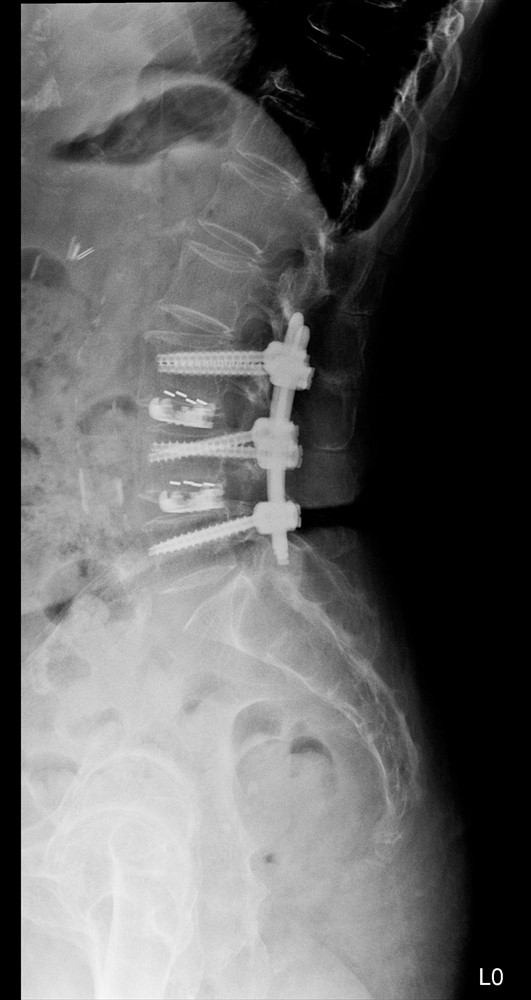

醫療技術能改變身體狀況,醫療團隊的陪伴,也往往能改變病人的人生。接受微創手術的七十九歲趙女士,手術前,就經歷了一段身心交織的艱難時刻。她在左膝關節手術後約四十天外出購物時不慎跌倒。之後逐漸出現臀部、左大腿與腰部疼痛。她形容彎腰時痛得最為劇烈,甚至需要別人攙扶才能站起來。就在忍受身體疼痛的同時,相伴五十六年的丈夫也不幸過世。

兒子與孫子每晚上來陪伴,她告訴自己必須振作,不能讓家人擔心。來到台中慈濟醫院神經醫學中心求診,醫療團隊親切的態度讓原本害羞緊張的她逐漸放下心防。檢查後,顯示「腰椎第三、四、五節滑脫」,是造成劇痛的原因。

醫療團隊安排「腰椎微創骨釘融合與可撐開式墊片手術」,手術順利完成後,她的臀部刺痛與彎腰不適幾乎完全消失。如今趙女士重新找回生活節奏。每天會拄著單手杖外出散步一小時,還能做一百下深蹲運動。白天偶爾和女兒逛街,晚上有兒孫陪伴。孫子甚至笑說,阿嬤看起來比實際年齡年輕許多。

近八十歲的趙女士的腰痛是腰椎第三、四、五節滑脫,經台中慈濟醫院神經醫學中心手術治療後恢復,且更顯年輕了。左圖為術前、右圖為術後。